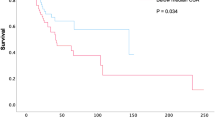

The strongest correlation of thoracic SMI at the different thoracic levels with the widely used L3 SMI was at the T12 level (Table 2). This was followed, in descending order, by total unilateral AbvAoAr, T8, and pectoralis unilateral AbvAoAr. The T12 level persisted as the strongest correlation after sex-stratification (Fig. 3), but T8 was better than total unilateral AbvAoAr in men (r = 0.787 vs. r = 0.771), and pectoralis unilateral AbvAoAr was better than T8 in women (r = 0.609 vs. r = 0.567). A trend similar to SMI applied to IMAT%. The strongest correlation was at T12, followed by total unilateral AbvAoAr and T8; the correlation was weak at pectoralis unilateral AbvAoAr (Table 2).